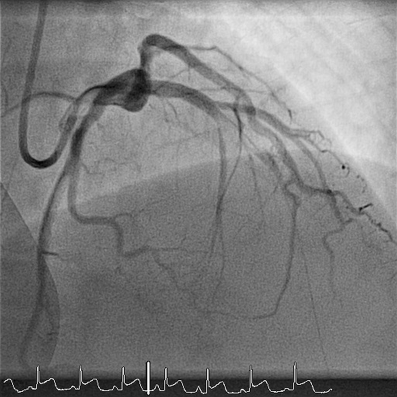

A coronary angiography of patient 2, showing an occlusion of the left main coronary artery and a dissection of the left anterior descending artery and circumflex coronary artery